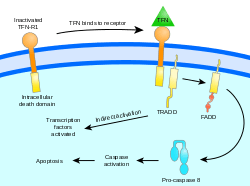

Two theories of the direct initiation of apoptotic mechanisms in mammals have been suggested: the TNF-induced (tumour necrosis factor) model and the Fas-Fas ligand-mediated model, both involving receptors of the TNF receptor (TNFR) family[31] coupled to extrinsic signals.

TNF path

TNF-alpha is a cytokine produced mainly by activated macrophages, and is the major extrinsic mediator of apoptosis. Most cells in the human body have two receptors for TNF-alpha: TNFR1 and TNFR2. The binding of TNF-alpha to TNFR1 has been shown to initiate the pathway that leads to caspase activation via the intermediate membrane proteins TNF receptor-associated death domain (TRADD) and Fas-associated death domain protein (FADD). cIAP1/2 can inhibit TNF-α signaling by binding to TRAF2. FLIP inhibits the activation of caspase-8.[32] Binding of this receptor can also indirectly lead to the activation of transcription factors involved in cell survival and inflammatory responses.[33] However, signalling through TNFR1 might also induce apoptosis in a caspase-independent manner.[34] The link between TNF-alpha and apoptosis shows why an abnormal production of TNF-alpha plays a fundamental role in several human diseases, especially in autoimmune diseases.